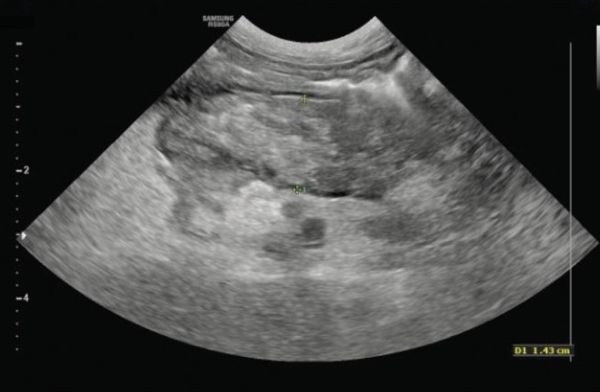

Aside from possible hypoglycaemia, it is common for the findings of complete blood count, serum biochemistry and urinalysis to be completely normal in dogs with insulinoma. Mild hypokalaemia and/or mildly increased alanine transaminase (ALT) activity have been reported in some cases.5 Thoracic and abdominal imaging are recommended in all dogs with suspected insulinoma, to assess for the presence of a pancreatic mass and to screen for metastatic disease. Thoracic and abdominal radiography is usually normal in dogs with insulinoma.5,15,16 Abdominal ultrasound is more sensitive, with approximately 56% of dogs with insulinoma having an ultrasonographically-detectable pancreatic mass (Figure 1).3,4,15 Dual-phase computed tomography (CT) appears to be the most effective means of identifying a pancreatic mass, with a reported sensitivity of 71%.17

Figure 1: Sonographic image of a pancreatic mass in a dog with insulinoma.